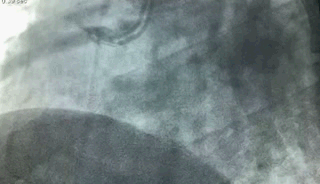

冠状动脉造影

上图)右冠状动脉的中远段发生了急性闭塞,心肌梗死就是这样产生的。